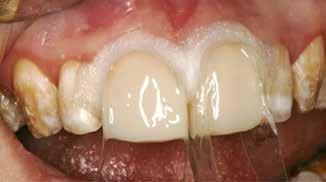

Fig. 1. 40-årig sund og rask mand møder bekymret for sine slidte tænder. Klinisk ses frakturer og substanstab langs incisalkanterne på overkæbetænderne.

Fig. 1. A 40-year-old healthy man is concerned for his worn teeth. Clinically, fractures and loss of tooth substance are observed at the incisal edge of the upper front teeth.

Okklusalt billede af A) over- og B) underkæbe

2. Klinisk ses tydelig slitage ind i dentinen på samtlige tænder fra 6’er til 6’er i begge kæber.

Fig. 2. Clinically, extensive wear into the dentin of all teeth in both jaws is observed.

Klinisk undersøgelse viste et tandsæt med enkelte restaureringer, men med slitagedefekter okklusalt/incisalt på samtlige tænder fra 6’er til 6’er i over- og underkæbe (Fig. 2). Defekterne strakte sig tydeligt ind i dentinen. Baseret på anamnesen og de kliniske fund blev erosion set som hovedårsagen til tandsliddet, mens attrition formodedes at være en medvirkende faktor.

okklusal-vertikale dimension. De afficerede dentinoverflader blev ridset i overfladen med en grov diamant, men derudover blev der ikke foretaget nogen form for kavitetspræparation, da intentionen var at gennemføre en minimalt invasiv behandlingstilgang. Kofferdam blev anlagt i hvert arbejdsfelt (Fig. 3) og adhæsivet påført med en æts-og-skyl-strategi (ætsning af emalje og dentin, primer, adhæsiv). Derefter blev tænderne bygget op med en mikrohybrid komposit for at genskabe tandens naturlige form (Fig. 4). I underkæbefronten blev der kun lagt et tyndt lag med komposit pga. pladsmangel. Efter omhyggelig pudsning og polering havde patienten okklusion på samtlige tænder og var tilfreds med både funktion og æstetik.

Fig. 4. Færdigrestaurerede tænder med komposit.

Fig. 4. Final restored teeth with composite.